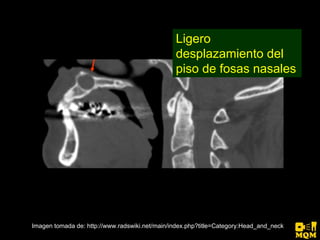

El quiste nasopalatino es un quiste embrionario situado en la línea media en la parte anterior del paladar, que se origina de los restos del conducto nasopalatino. Generalmente aparece entre los 40-60 años y se presenta como un aumento de volumen blando y no doloroso entre los incisivos centrales superiores que puede causar divergencia radicular. Las características radiográficas incluyen una lesión radiolúcida, bien delimitada y de forma redondeada u ovalada que cruza la línea media maxilar.